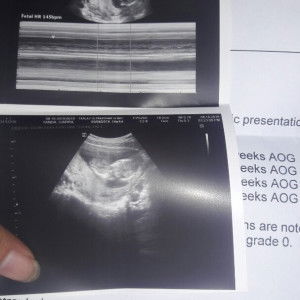

Got a bun in the oven